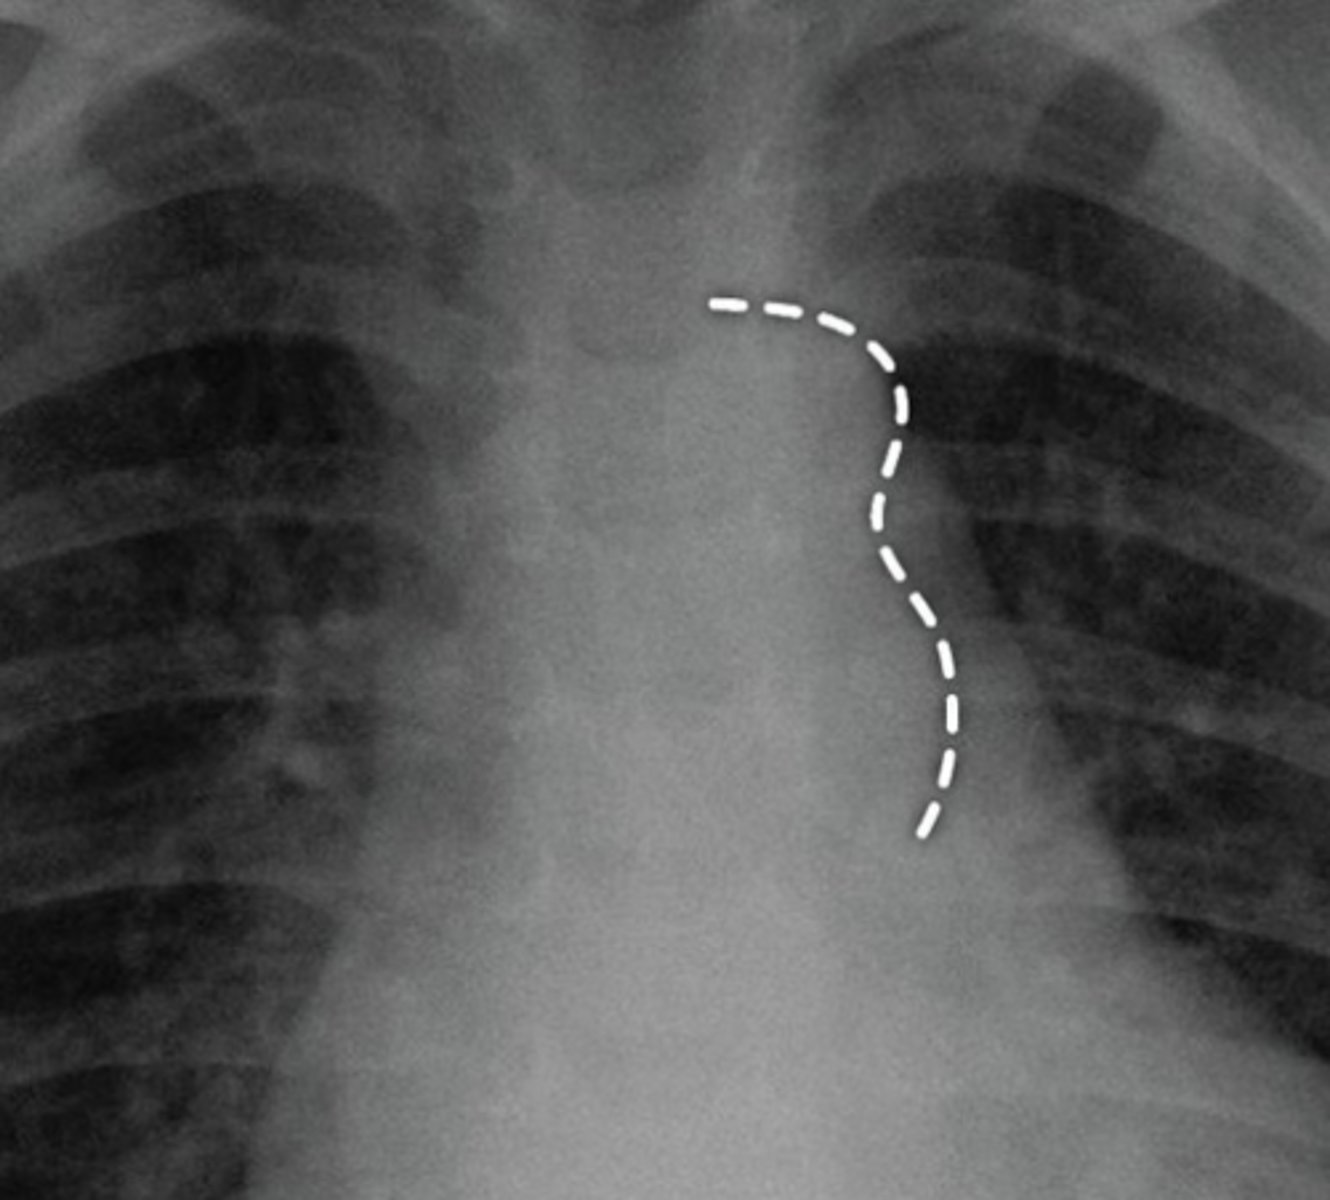

What is the chest radiograph finding in coarctation of the aorta?

Figure 3 sign.

<p>Figure 3 sign.</p>

82